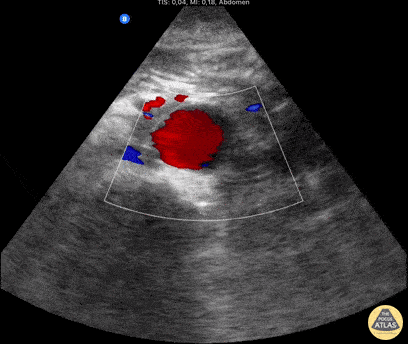

Uncomplicated, nonthrombosed, 3-cm aneurysm of the abdominal aorta Ivan Rancano Garcia